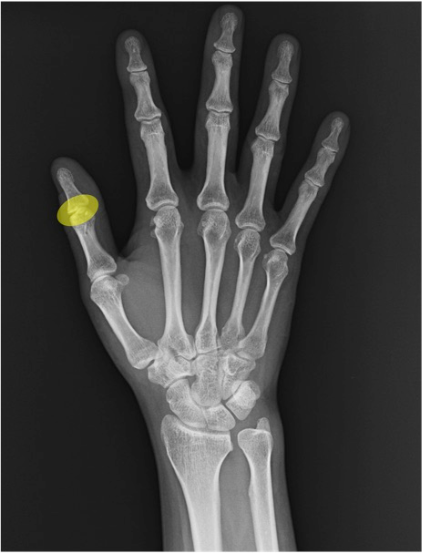

IP関節(interphalangeal joint)

指節骨間の関節。母指はIPのみで、他指のPIP/DIPに相当。正面像で裂隙幅と骨棘・骨硬化の有無に注目。